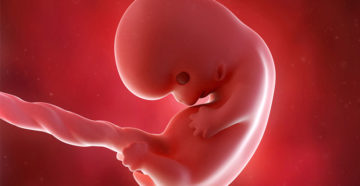

8 неделя беременности. Плод 8 недель Восьмую неделю беременности еще также называют шестой эмбриональной неделей….

8 неделя беременности Наверняка вы уже думали над именем ребенка и не раз гадали, мальчик…

8 неделя беременности: что происходит с малышом и мамой, ощущения, развитие плода Каждая неделя беременности…